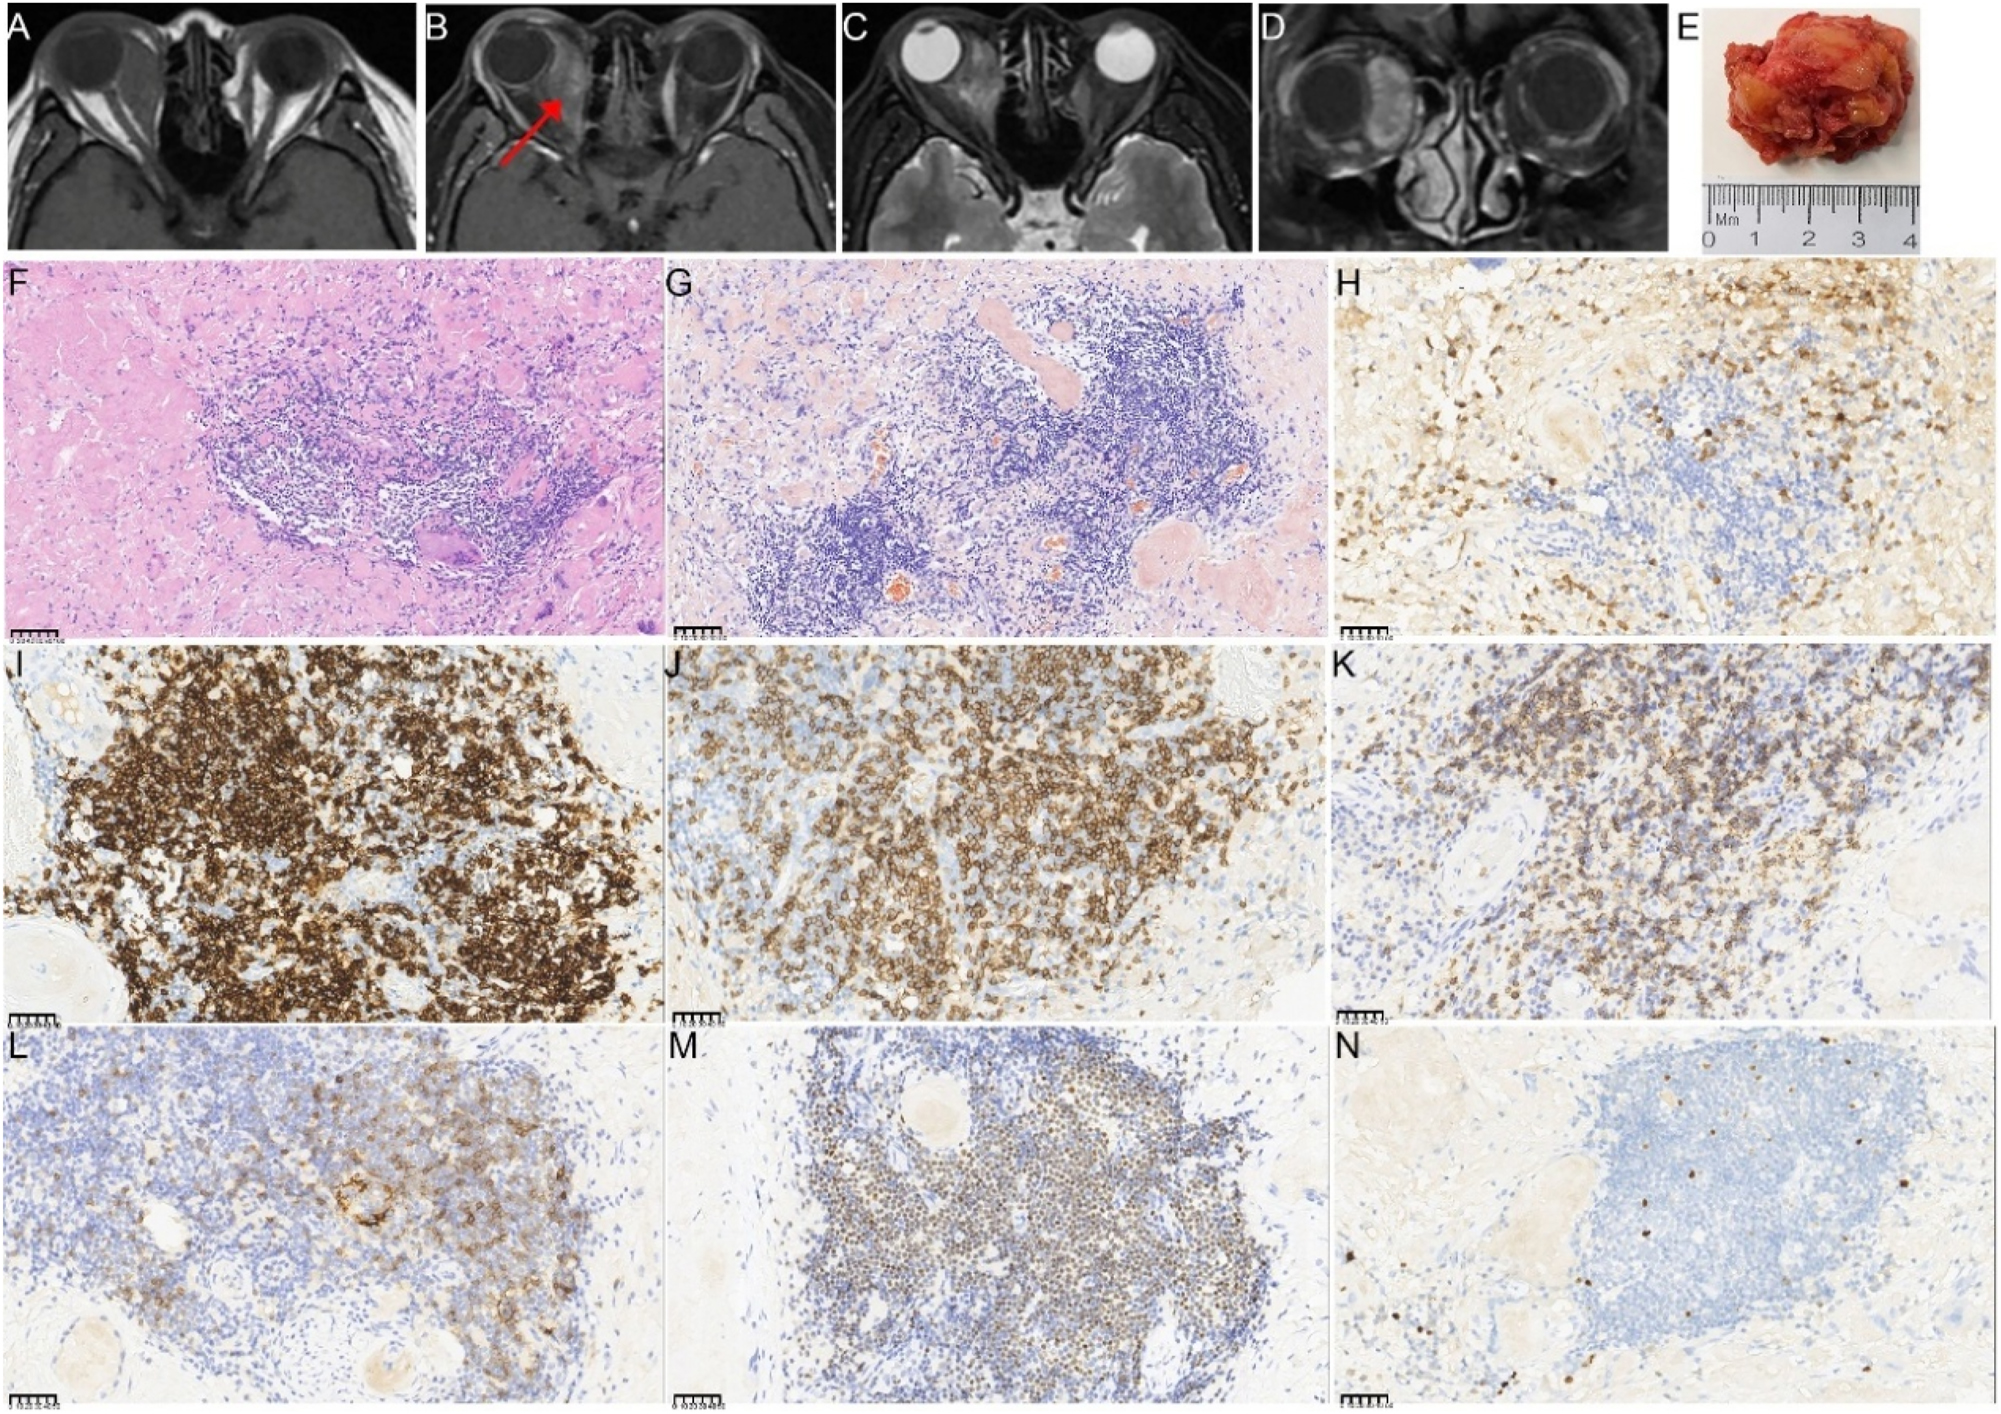

A 41-year-old woman presented with a 1-year history of right eye proptosis and restricted ocular motility. The patient’s visual acuity was 20/40 in both eyes, and the right eye exhibited pronounced proptosis, limited motility in horizontal directions, and bulbar conjunctival congestion and edema (Figure 2A). Computed tomography (CT) scan revealed fusiform enlargement of the right medial rectus muscle, whereas the tendons remained unaffected (Figure 2B and C). The pathological diagnosis indicated amyloidosis, with a significant increase in IgG4-positive cells (Figure 2D–I). The patient’s recent serum IgG4 level was 0.944 g/L, which was within the reference range of 0.03–2.01 g/L. The patient did not undergo any treatment regimen and was advised to attend regular follow-ups. One year later, the patient exhibited further enlargement of the medial rectus muscle of the right eye (Figure 2A), accompanied by a decline in visual acuity to 20/50 in the affected eye. Orbital contrast-enhanced magnetic resonance imaging (MRI) revealed an enlarged medial rectus muscle in the right eye with mixed intensity, and the maximum cross-sectional area of the tumor was approximately 2.92×1.43 cm (Figure 3A–D). A second surgical procedure was necessary, and the resected specimen appeared as hard, brittle, yellow-white masses (Figure 3E). Immunohistochemical staining (IHC staining) revealed 0–90 IgG4+cells per high-power field (HPF) in the lesion (Figure 3H). IHC staining confirmed MALT lymphoma, showing positive expression for CD20, CD3, CD5 (Figure 3I–M) and CD23 (FDC), and negative expression for CD10, Cyclin D1, CD1a, ALK, S100, Langerin, and BRAF V600E. Ki-67 staining indicated a low proliferative index of 5–10 % (Figure 3N). No clonal IgH and IgK rearrangements were detected. In addition, her serum IgG4 levels were within the normal range. Whole-body imaging revealed no signs of systemic disease. Consequently, a definitive diagnosis of orbital MALT lymphoma with primary amyloidosis was established. The patient underwent successful treatment with three-dimensional conformal radiotherapy (3DCRT), with a total dose of 30 Gy administered in 10 fractions using 6 MV photons. Follow-up orbital MRI one year later showed a significant reduction in tumor size, with the maximum cross-sectional area decreasing from 2.3×0.8 cm–2.3×0.57 cm (Figure 4A–C). However, fundus examination revealed macular edema in the right eye, for which the patient received a Dexamethasone Intravitreal implant (Ozurdex, Allergan Pharmaceuticals, Ireland). This condition may be a side effect of radiotherapy, and the patient remains under ongoing follow-up.

The orbital imaging, gross specimen, and pathological images of the lesion specimen in the second surgery (A–D) preoperative enhanced MRI of the orbit before the second surgery. The right retrobulbar lesions appear hyperintense with uneven enhancement on contrast imaging, surrounding the right optic nerve and right eyeball. The red arrows indicate the right enlargement of the medial rectus muscle (E) gross appearance of the resected tumor, which was whitish, hard, and measured approximately 3.5×3×1.5 cm in total volume (F–N) histopathological findings from the second surgery (F) lower magnification showing amyloidosis with a foreign body reaction and focal lymphocyte and plasma cell infiltration (HE; 200×) (G) Congo red staining of the orbital lesion demonstrates a positive result under microscopy at 400×magnification (H) IHC staining for IgG (400×), showing infiltration of a few IgG4-positive plasma cells (I) partial positive CD 20 immunostaining of tumor cells (400×) (J) Partial positive CD3 immunostaining of tumor cells (400×) (K) Partial positive cytoplasmic CD5 immunostaining of tumor cells (400×) (L) A few tumor cells showed positive CD23 immunostaining of tumor cells (400×) (M) Partial positive OCT2 immunostaining of tumor cells (400×) (N) Ki67 immunostaining demonstrates strong nuclear immunoreactivity in approximately 5–10 % of tumor cells (400×). The unit of scale bar is μm.

Orbital imaging of the lesion after the second surgery (A, B) enhanced MRI of the orbit 2 weeks after the second surgery shows a significant reduction in lesion size compared with the preoperative size. The maximum cross-sectional area of the tumor measured approximately 2.3×0.8 cm (C) Enhanced MRI of the orbit 6 months after radiotherapy, demonstrating further tumor shrinkage, with a maximum cross-sectional area of approximately 2.3×0.57 cm.